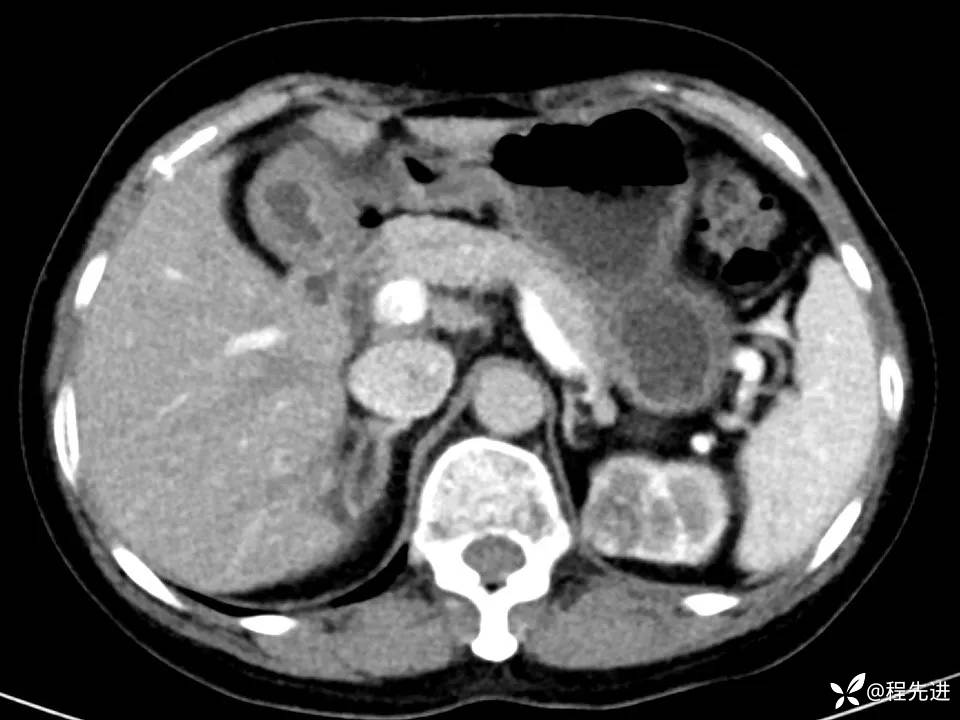

患者性别:女

患者年龄:67岁

简要病史:体检发现左肾占位,无临床症状,实验室检查无殊。

CT、MRI平扫+增强: